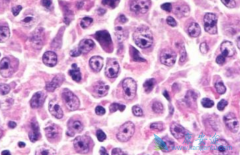

日前,IMV公司宣布已扩大其临床计划的第二阶段篮子试验,评估其主要候选药物DPX-Survivac,结合低剂量环磷酰胺和默沙东抗PD-1疗法 KEYTRUDA (pembrolizumab,帕博利珠单抗)用于晚期或复发性实体瘤患者的治疗效果。   IMV公司首席执行官Frederic Ors ...